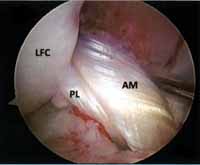

完全型円板状半月遊離縁

右:円板状半月